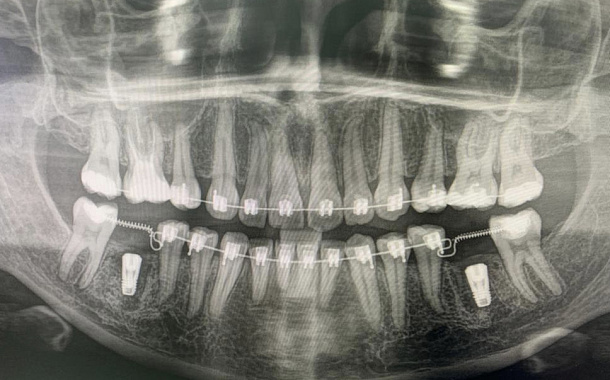

По 3D компьютерной томографии определяет возможность установки имплантата, немедленной фиксации временной коронки в день операции и объем пластических манипуляций. Совместно с врачом-стоматологом ортопедом планирует вид ортопедической конструкции и положение имплантата.

Компьютерная томография в формате 3D - важный диагностический инструмент стоматолога. На полученном объемном снимке стоматолог видит все нюансы вашей зубочелюстной системы: состояние костной ткани челюстей, зубов и височно-нижнечелюстного сустава. Именно томография позволяет доктору составить план и объем предстоящего оперативного вмешательства.

Обязательным условием подготовки к имплантации является снятие слепков и изготовление диагностических моделей для планирования и изготовления временной ортопедической конструкции, а в определенных условиях хирургического шаблона. Хирургический шаблон — накладка из пластмассы на зубной ряд с отверстиями для имплантатов. Благодаря шаблону хирург Немецкого Стоматологического Центра устанавливает имплантат в заранее спланированное положение, не нарушая траекторию ни на миллиметр.